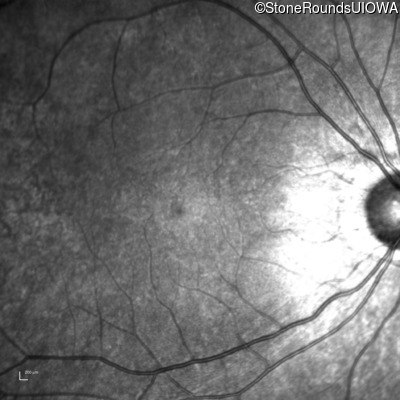

Infrared Fundus Photograph - Left - 20/30 +2

Exemplar